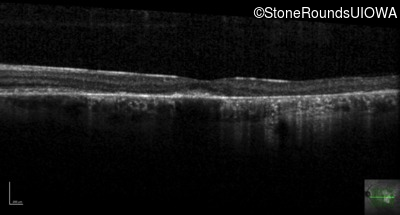

Age at visit: 38 years

OD OS

This 38 year old man first noticed poor vision in dim light when he was five years old. His visual acuity began to fall in his early 30's.